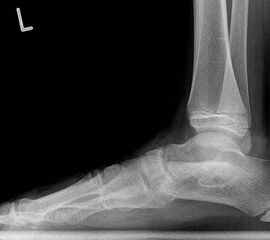

Die bildgebende Primärdiagnostik ist die Röntgen-Übersichtsaufnahme des Fußes im seitlichen, dorsoplantaren und schrägen Strahlengang. Weitere in der Literatur beschriebene Röntgen-Spezialeinstellungen sind durch die modernen dreidimensionalen Verfahren überholt.

In der Bildgebung ist bei dieser Form häufig eine einfache Röntgenschrägaufnahme (Abb. 8) ausreichend. Kombinationen mit talocalcanearer Coalitio werden beobachtet und sollten im Verdachtsfall ausgeschlossen werden. Für die Therapie wesentlich ist im Jugendlichen- und Erwachsenen-Alter das Ausmaß der degenerativen Veränderungen im Bereich des Talonavicular-Gelenkes.

Diagnostisch sollte neben Röntgenübersichtsaufnahmen (indirekte radiologische Zeichen: Dorsaler Traktions-Osteophyt am Taluskopf, „talar beaking“; kontinuierliche Linie der Trochlea-tali-Kontur übergehend in die Sustentaculum-tali-Kontur, „C-Zeichen“ (Abb. 11) 10) immer die dreidimensionale Bildgebung eingesetzt werden. Das MRT (mit Kontrastmittel) kann die Struktur der Brückenbildung und z.B. die Qualität des Restgelenkes (Knorpel-Dicke) besonders gut abbilden; das Dünnschicht-CT zeigt die knöcherne Feinstruktur im Bereich der Coalitio und den oft sehr schrägen Spalt-Verlauf im Frontalschnitt dagegen häufig genauer. Meist findet sich die Überbrückung im Bereich der medialen Facette; die Schichten sollten jedoch bis weit nach dorsal beurteilt werden, da ansonsten dorsomediale Formen übersehen werden können. Rozansky et al 7 unterschieden fünf morphologische Typen auf der Basis von 3-D-CT-Rekonstruktionen. Allerdings ist eine prognostische Zuordnung bisher nicht möglich.